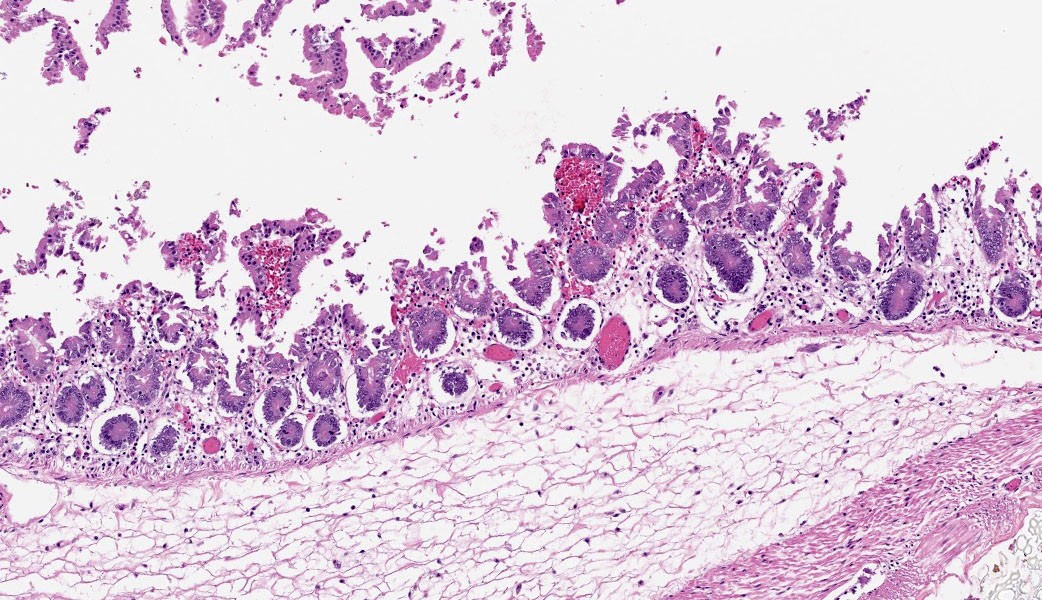

Cecum at ileocecocolic junction: One full-thickness cross sections of cecum at the ileocecocolic junction are examined from each animal (2 total). Diffusely, the submucosa is expanded by clear space (edema) and admixed inflammatory cells (neutrophils, macrophages, lymphocytes, and fewer plasma cells). The lamina propria is multifocally expanded by edema, hemorrhage, the previously mentioned admixed inflammatory cells, and karyorrhectic debris. The overlying epithelium has multifocal erosions and ulcerations with surface necrotic debris and mixed bacterial colonies.

Colon: Colitis, necrotizing, subacute, multifocal, moderate, with volcano lesions, hemorrhage, and severe submucosal edema.

Similar to Case 1, due to the presence of volcano lesions coupled with mucosal ulceration/necrosis and heterophilic inflammation, Dr. Uzal says this is C. difficile until proven otherwise! This case had some solid examples of volcano lesions in which heterophils could be seen exploding out of tiny ulcers in the mucosa.

Histologically, the colon was severely edematous and had gram-positive bacilli present within areas of mucosal necrosis that showed up beautifully on a Gram stain performed by Dr. Uzal’s lab. A secondary bacterial infection was considered by conference participants in the markedly dilated sections of gut in this case, especially since rabbits frequently have multispecies enteric infections similar to cattle (i.e. coronavirus, rotavirus, C. difficile, E. coli, etc.), but there was no laboratory testing available to confirm this. C. difficile, however, was confirmed by the contributor via ELISA for A/B toxin.